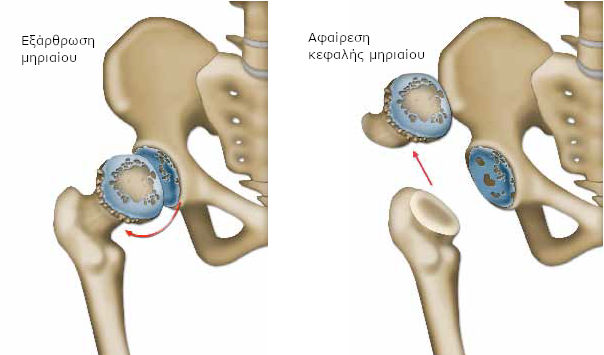

Ο χειρουργός «κόβει», βάσει προηγούμενων υπολογισμών, το ανώτερο τμήμα του μηριαίου (κεφαλή μηριαίου), που παρουσιάζει φθορά του χόνδρου και το αφαιρεί.

Με ειδικές ράσπες δημιουργεί, στη συνέχεια, στο εσωτερικό του μηριαίου ένα τούνελ, για να τοποθετήσει το πρώτο τμήμα της πρόθεσης. Εάν η κοιλότητα στη λεκάνη (κοτύλη) παρουσιάζει σοβαρές βλάβες εξαιτίας της αρθρίτιδας, ο χειρουργός προετοιμάζει επίσης το οστό, αφαιρώντας το χόνδρο με ειδικές ράσπες διαφόρων μεγεθών.

Όταν πρέπει να αντικατασταθούν όλα τα μέρη της άρθρωσης (ολική πρόθεση), ο χειρουργός προσθέτει ένα τμήμα σε σχήμα κούπας (το κυπέλλιο), που στερεώνεται στην κοτύλη.